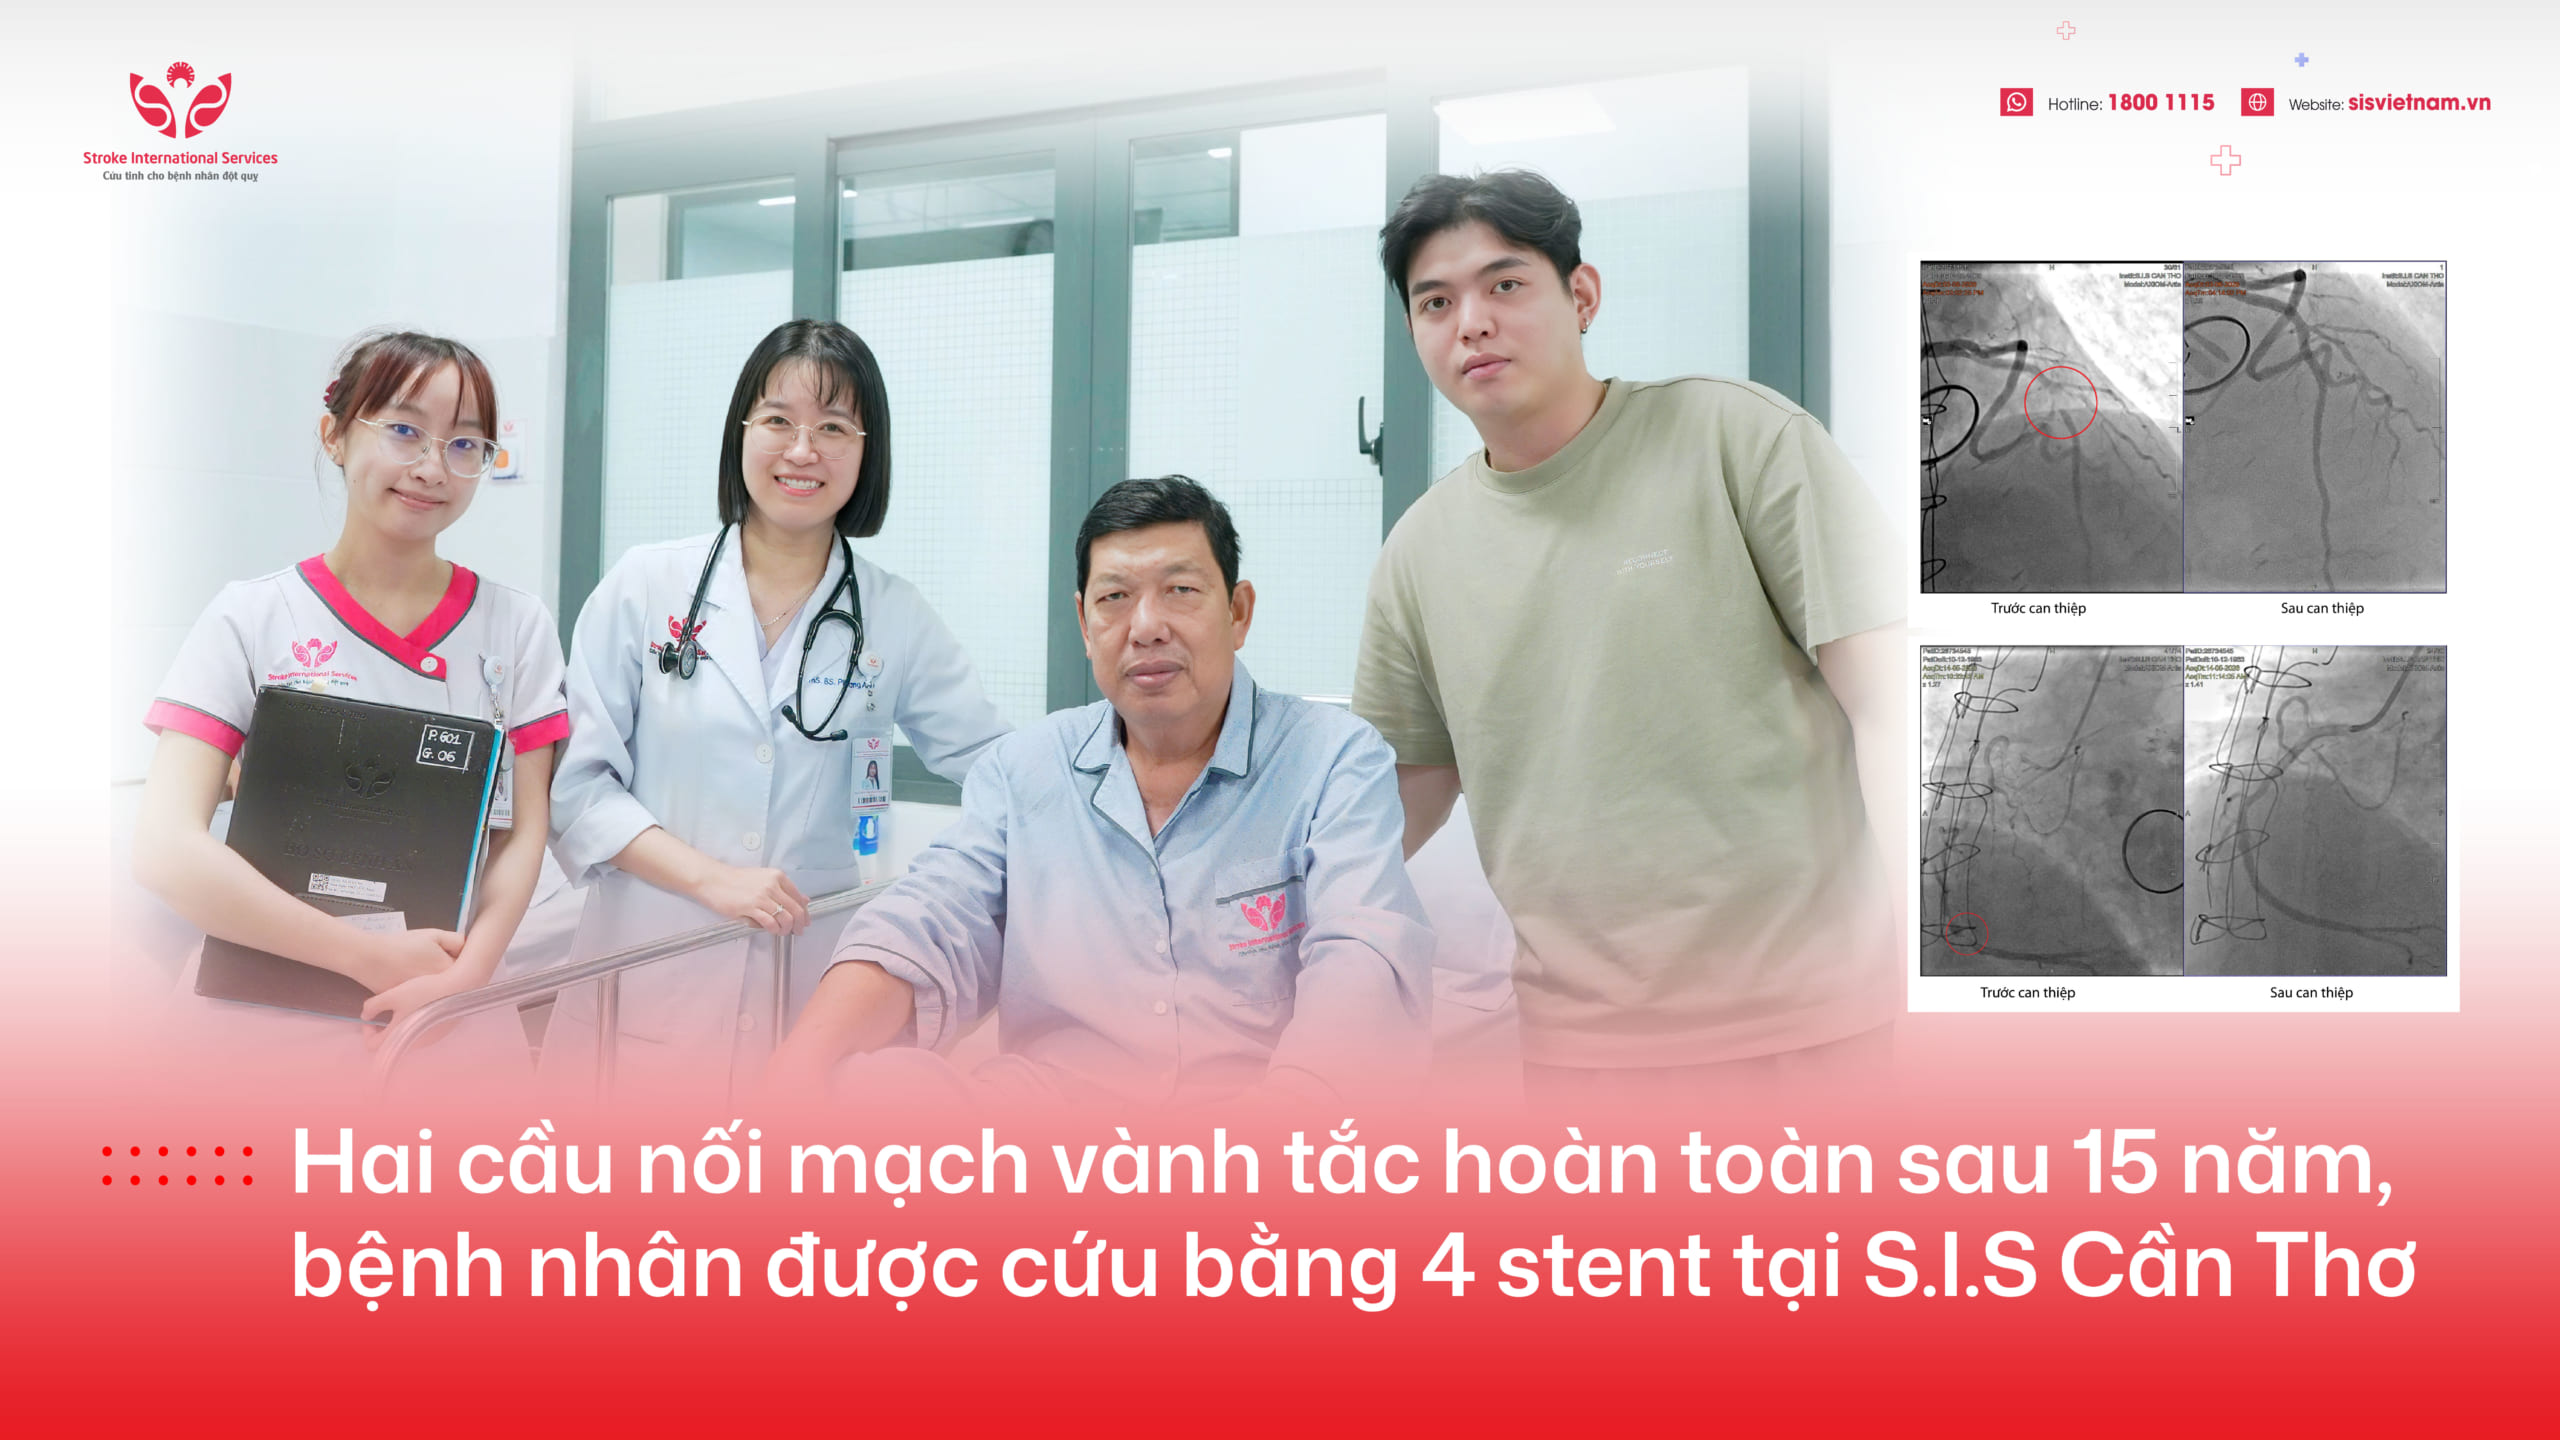

Anh Đ.T.A., sinh năm 1982 tại Thái Nguyên, đã trải qua đột quỵ cách đây 6 năm, sự thiếu may mắn của anh khi không được cấp cứu kịp thời đã qua giờ vàng, dẫn đến di chứng tổn thương não trái gây nói khó.

Chị T, vợ anh T.A., cho biết 6 năm trước, sau khi đột quỵ thì khả năng viết, đọc và nói của anh bị ảnh hưởng nghiêm trọng. Có khi không nói được từ nào, có khi chỉ nói được từng từ ngắn đơn giản như ăn, cơm, ngủ, tắm,… Gia đình anh đã không ngừng nỗ lực điều trị tại nhiều bệnh viện và tham gia vào các buổi tập vật lý trị liệu để phục hồi chức năng. Tuy nhiên, sau hơn 6 năm điều trị, tiến triển rất chậm gia đình khá bi quan. Tháng 10/2023, thông qua 1 người quen, gia đình biết đến S.I.S Cần Thơ và quyết định đưa anh từ Thái Nguyên vào Bệnh viện ĐKQT S.I.S Cần Thơ điều trị.

Sau 3 tháng điều trị ngày 06/01/2024, anh T.A đến S.I.S Đà Nẵng để tái khám lại. Sức khỏe của anh đã có sự cải thiện thần kỳ giờ đây anh T.A. không chỉ có thể nói được những từ dài hơn, mà còn có thể viết chữ như bình thường, trở nên vui vẻ và tự tin hơn rất nhiều so với trước đây.

Chị T. nói thêm: “Ban đầu, chị chỉ mong anh T.A không bị tái phát đột quỵ, chứ không hy vọng quá nhiều về sự phục hồi. Nhưng sau khi điều trị theo phát đồ của S.I.S thì chị thấy rõ dấu hiệu phục hồi của anh được tính từng ngày, có thể nói kết quả điều trị sau 3 tháng tại S.I.S phục hồi nhanh hơn 6 năm điều trị nhiều nơi sau khi anh bị đột quỵ, vượt qua những gì mong đợi của gia đình. Gia đình rất vui và cám ơn bác sĩ, càng vui hơn khi có S.I.S ở Đà Nẵng đã rút ngắn khoảng cách đi tàu 1000 cây số vào Sài Gòn rồi phải đi xe về Cần Thơ”.

TS.BS Trần Chí Cường chia sẻ: “Đây là trường hợp đột quỵ khá hiếm gặp! Bệnh nhân không bị yếu liệt mà chỉ bị ảnh hưởng đến chức năng ngôn ngữ: nói khó, viết khó, đôi khi không hiểu và không thể diễn đạt. Vị trí tổn thương trên não thường là thùy thái dương bên trái (trung tâm ngôn ngữ) với người thuận tay phải. Dạng đột quỵ này rất dễ bị bỏ sót và điều trị muộn màng vì triệu chứng thường nhẹ và diễn tiến từ từ. Tuy nhiên, nếu mức độ nặng có thể gây mất ngôn ngữ hoàn toàn ảnh hưởng nhiều đến chất lượng cuộc sống”